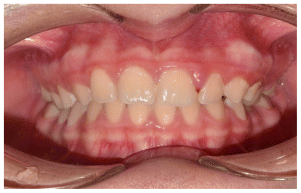

The patient was a 6-year-old female presenting with a Class III dento-skeletal malocclusion associated with anterior crossbite in the early mixed dentition (Figures 20–26). Baseline diagnostic records included orthopantomography, latero-lateral cephalometric radiography with cephalometric analysis, and extraoral and intraoral photographs. Clinical examination revealed a flat-to-slightly convex facial profile with sagittal skeletal discrepancy and negative overjet (Tables 5, 6). The treatment consisted exclusively of functional orthopedic therapy using the AMCOP® TC appliance, worn throughout the night and for one additional hour during the day, for a total duration of 24 months. At the end of active treatment, complete correction of the anterior crossbite was achieved, with normalization of overjet and overbite and establishment of a Class I dental relationship. A long-term follow-up evaluation performed at the age of 12 years, in complete permanent dentition, confirmed the stability of the results, showing a well-maintained anterior dental seal and a stable Class I occlusion. The AMCOP® TC appliance was continued as nighttime retention only, supporting neuromuscular balance and occlusal stability throughout growth.